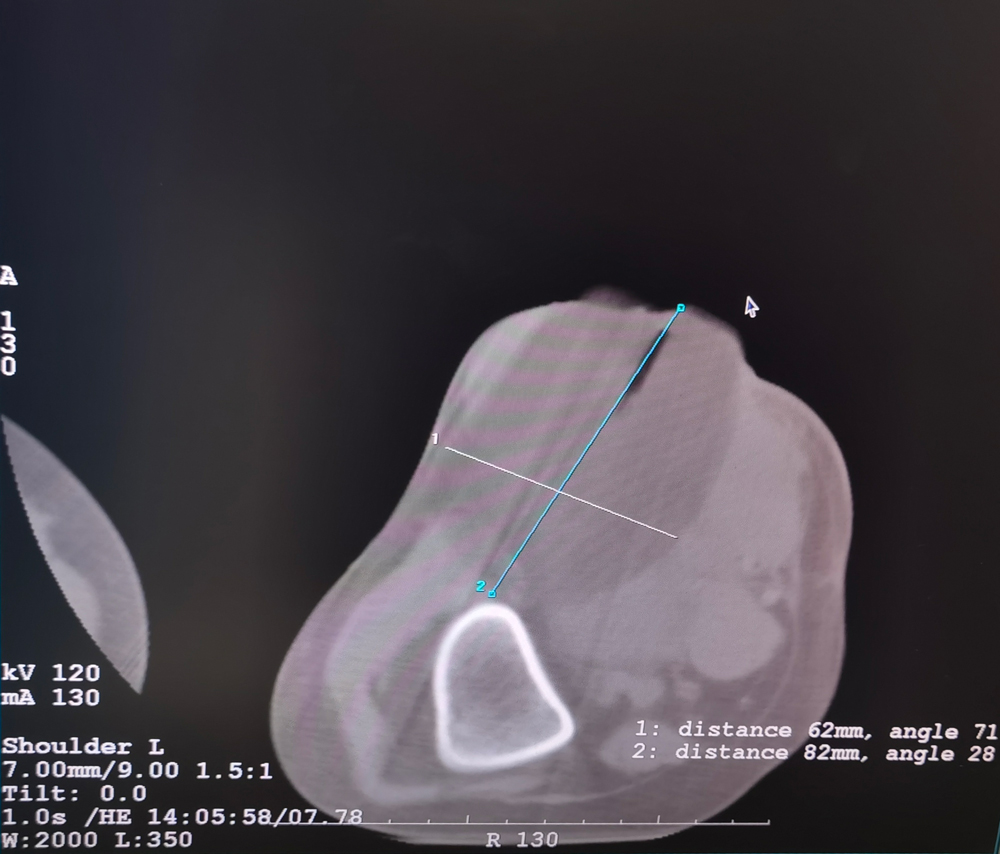

女,42歲,復發(fā)性脂肪瘤,病灶位于右側(cè)膝關(guān)節(jié),直徑大小13cm。采用雙針方案,共進行6個凍融循環(huán),最大冰球直徑達8.2cm,術(shù)中多方位治療全面覆蓋病灶范圍。患者術(shù)后狀況良好。